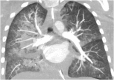

"Cases of SCMR" is a case series on the SCMR website (https://www.scmr.org) for the purpose of education. The cases reflect the clinical presentation, and the use of cardiovascular magnetic resonance (CMR) in the diagnosis and management of cardiovascular disease. The 2022 digital collection of cases are presented in this manuscript.